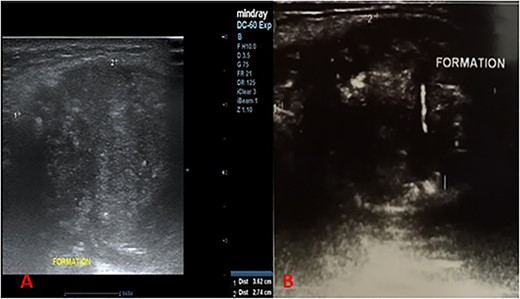

This was a 44-year-old female patient, with no specific pathological history, who consulted for a painless, median, anterior cervical swelling that had been progressively evolving for 2 and a half years. There was no evidence of dysphonia, dysphagia or cough. Physical examination revealed a median tumefaction, in contact with the sub-hyoid bone, oval in shape with a transverse major axis of about 6 cm, rising on swallowing and tongue protraction, painless, firm to palpation, regular in outline, with no inflammatory signs (Fig. 1). We suggested atypical TTC, dermoid cyst or ectopic thyroid nodule as diagnostic hypotheses, and requested further investigations. Cervical ultrasonography revealed a heterogeneous oval formation with internal calcifications, more or less regular contours, posterior reinforcement, relatively thick-walled, anterior cervical location, pushing back the muscles laterally and posteriorly, poorly vascularized on Doppler (Fig. 2A and B). The thyroid gland was normal in size, with a finely nodular echostructure.

Longitudinal cervical ultrasound sections showing a heterogeneous formation, with more or less regular contours, associated with microcalcifications (A) with liquid portions showing posterior enhancement (B).

In view of the close relationship with the hyoid bone, the frequency of TTCs in the anterior high cervical region and the presence of a cystic contingent within the lesion on ultrasound, the diagnosis of atypical TTC was retained.